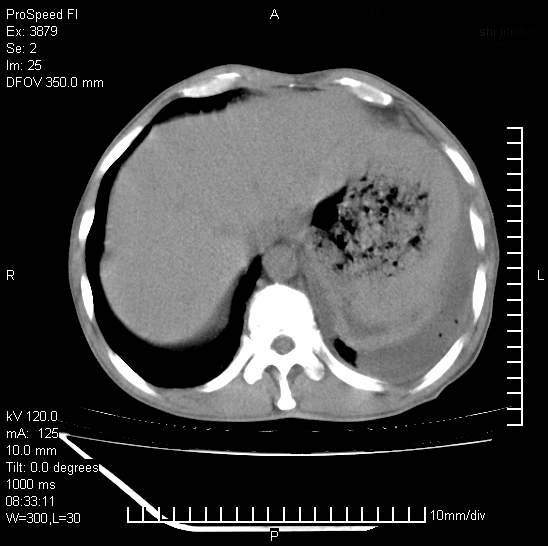

以下是引用37度在2008-6-6 11:20:00的发言:[br]1.包裹性积液,多考虑结核性;[br]2.穿刺术后改变。